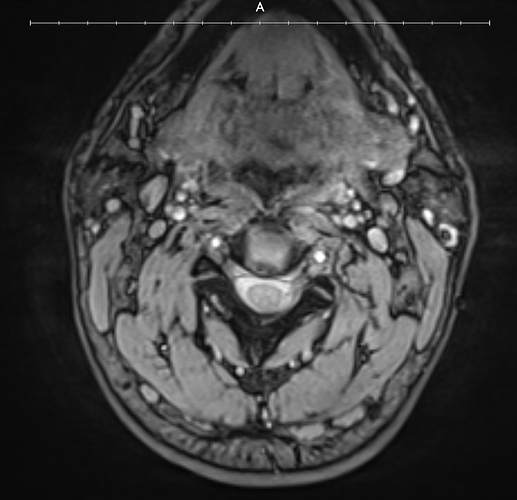

Here are my scans:

I want to get a second pair of eyes because I can clearly see the calcified ligaments he was talking about and it looks like my right IJV is being compressed but it is hard to tell. It also looks like the calcified ligament is compressing my left IJV a little bit.